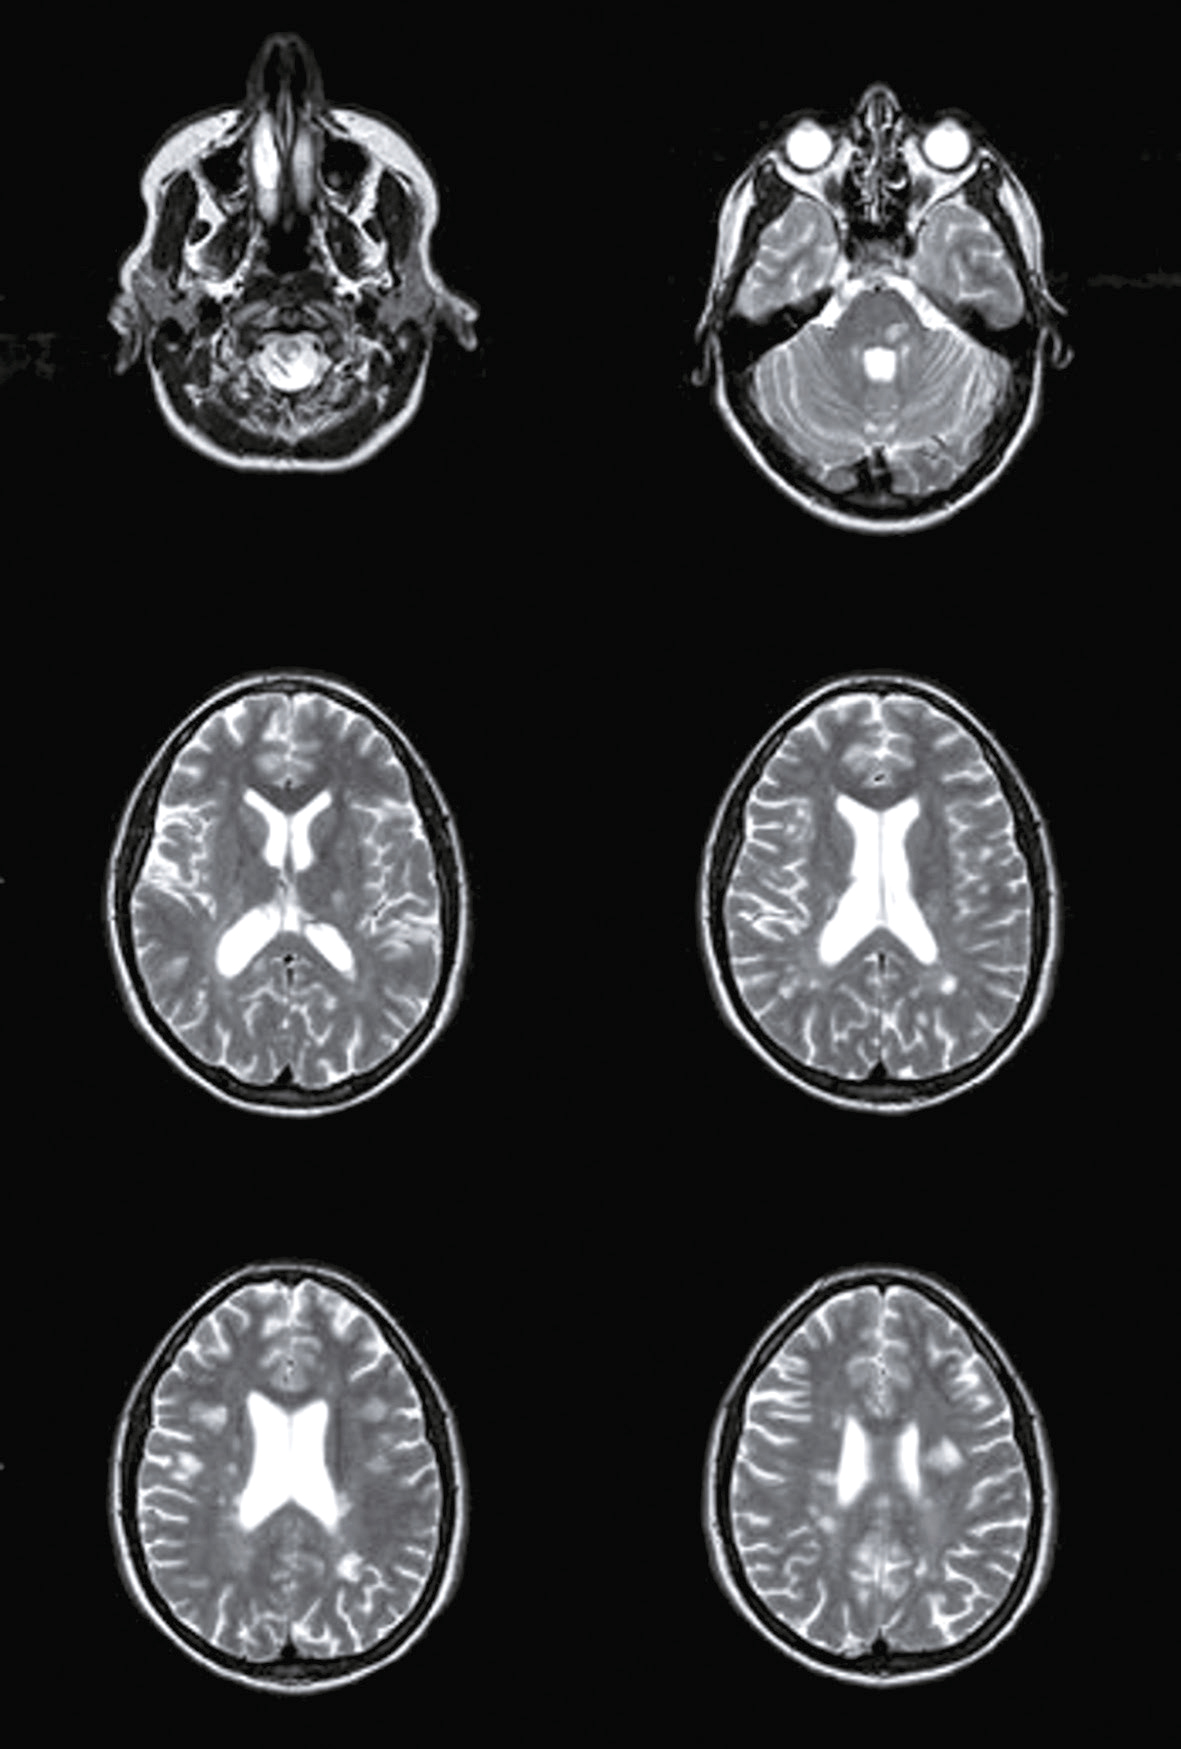

Une nouvelle IRM cérébrale est réalisée devant cette diplopie. Décrivez le cliché (fig. 31.1).

- C hypersignaux de la substance blanche périventricu-laire

- D hypersignaux du tronc cérébral

- E hypersignaux juxtacorticaux